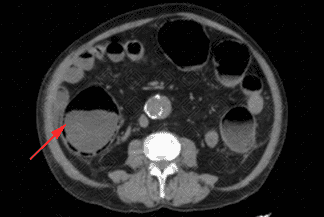

Texto alternativo para a imagem Créditos: Dra. Elazir Mota - Rio de Janeiro/RJ

Descrição das imagens: Tomografia computadorizada do abdome evidenciando importante distensão das alças de cólon ascendente e ceco, em associação com a presença de gás na parede destas alças (setas vermelhas), o que caracteriza a pneumatose intestinal.